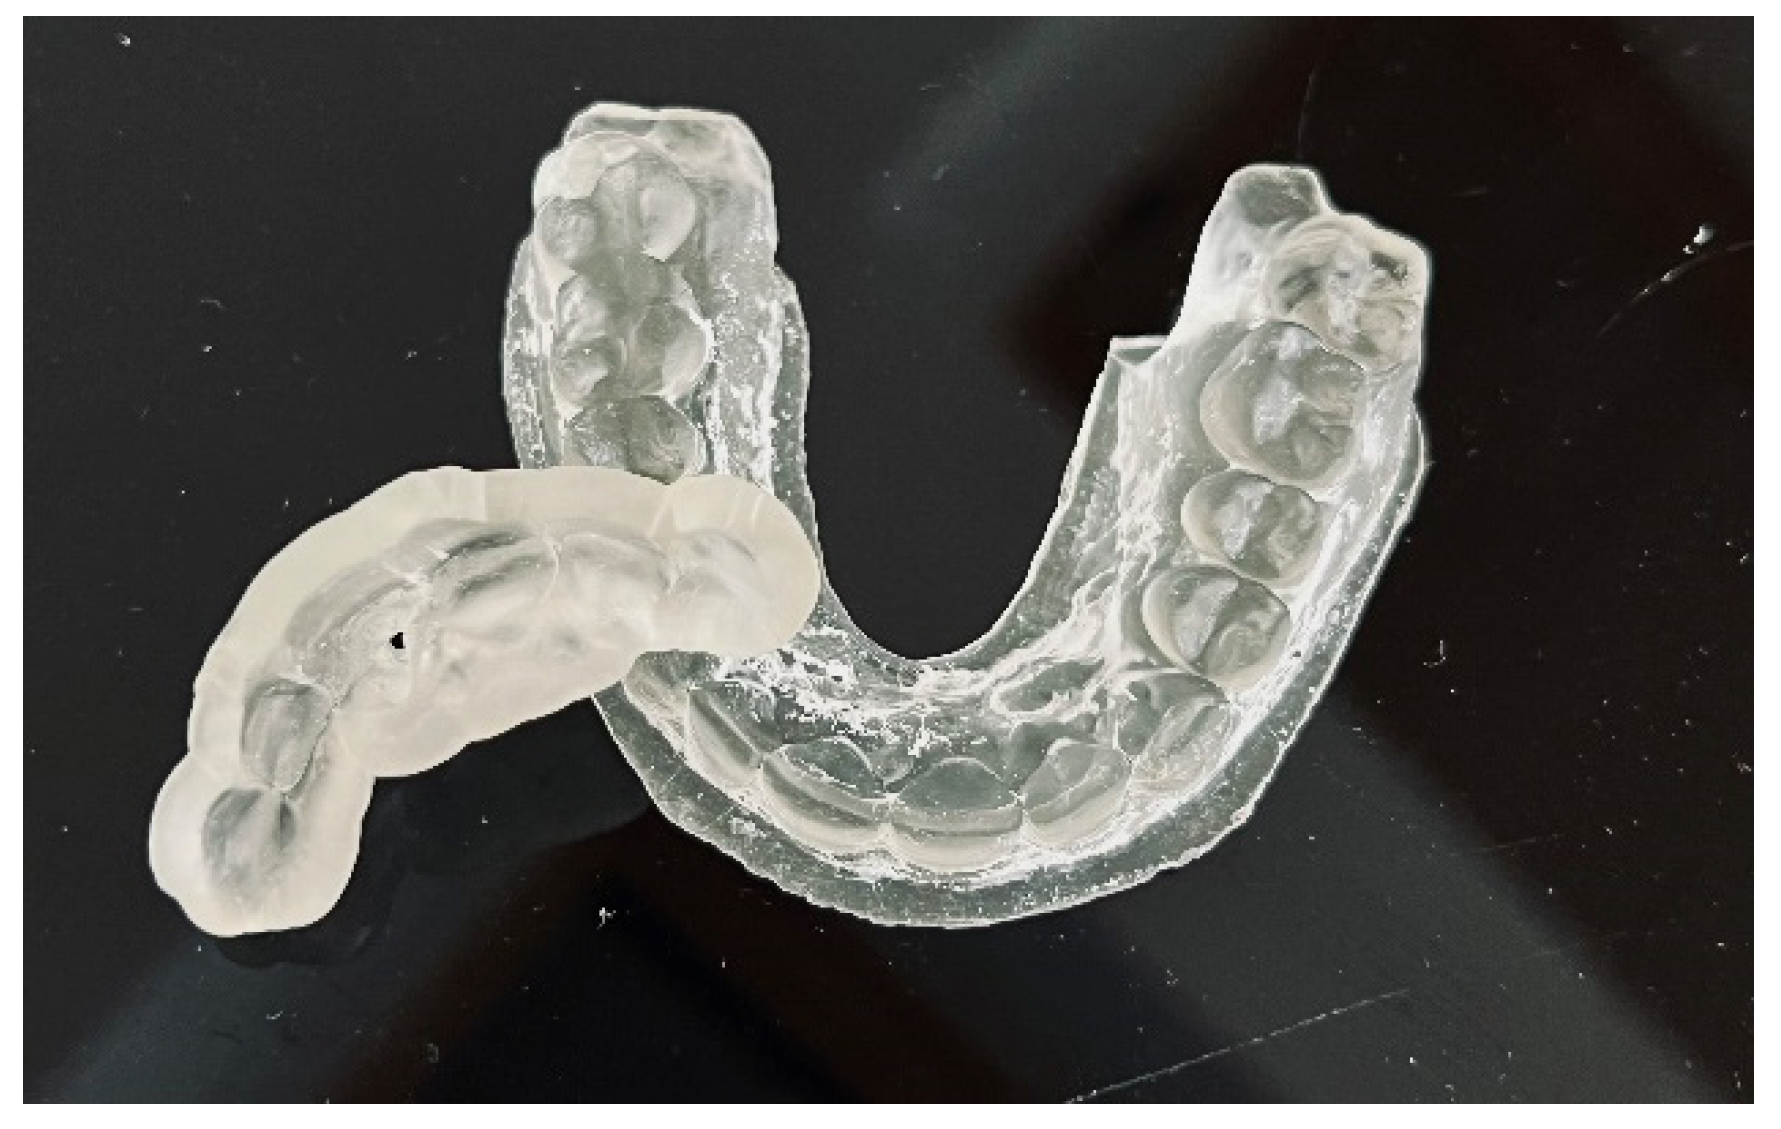

| Three-dimensional printing |

| Control the fit of the guide before and after placing rubber dam |

| Make a sign through the guide to indicate the access point in non-treated teeth |

| Remove the enamel until dentine is exposed |

| Place the guide on the teeth |